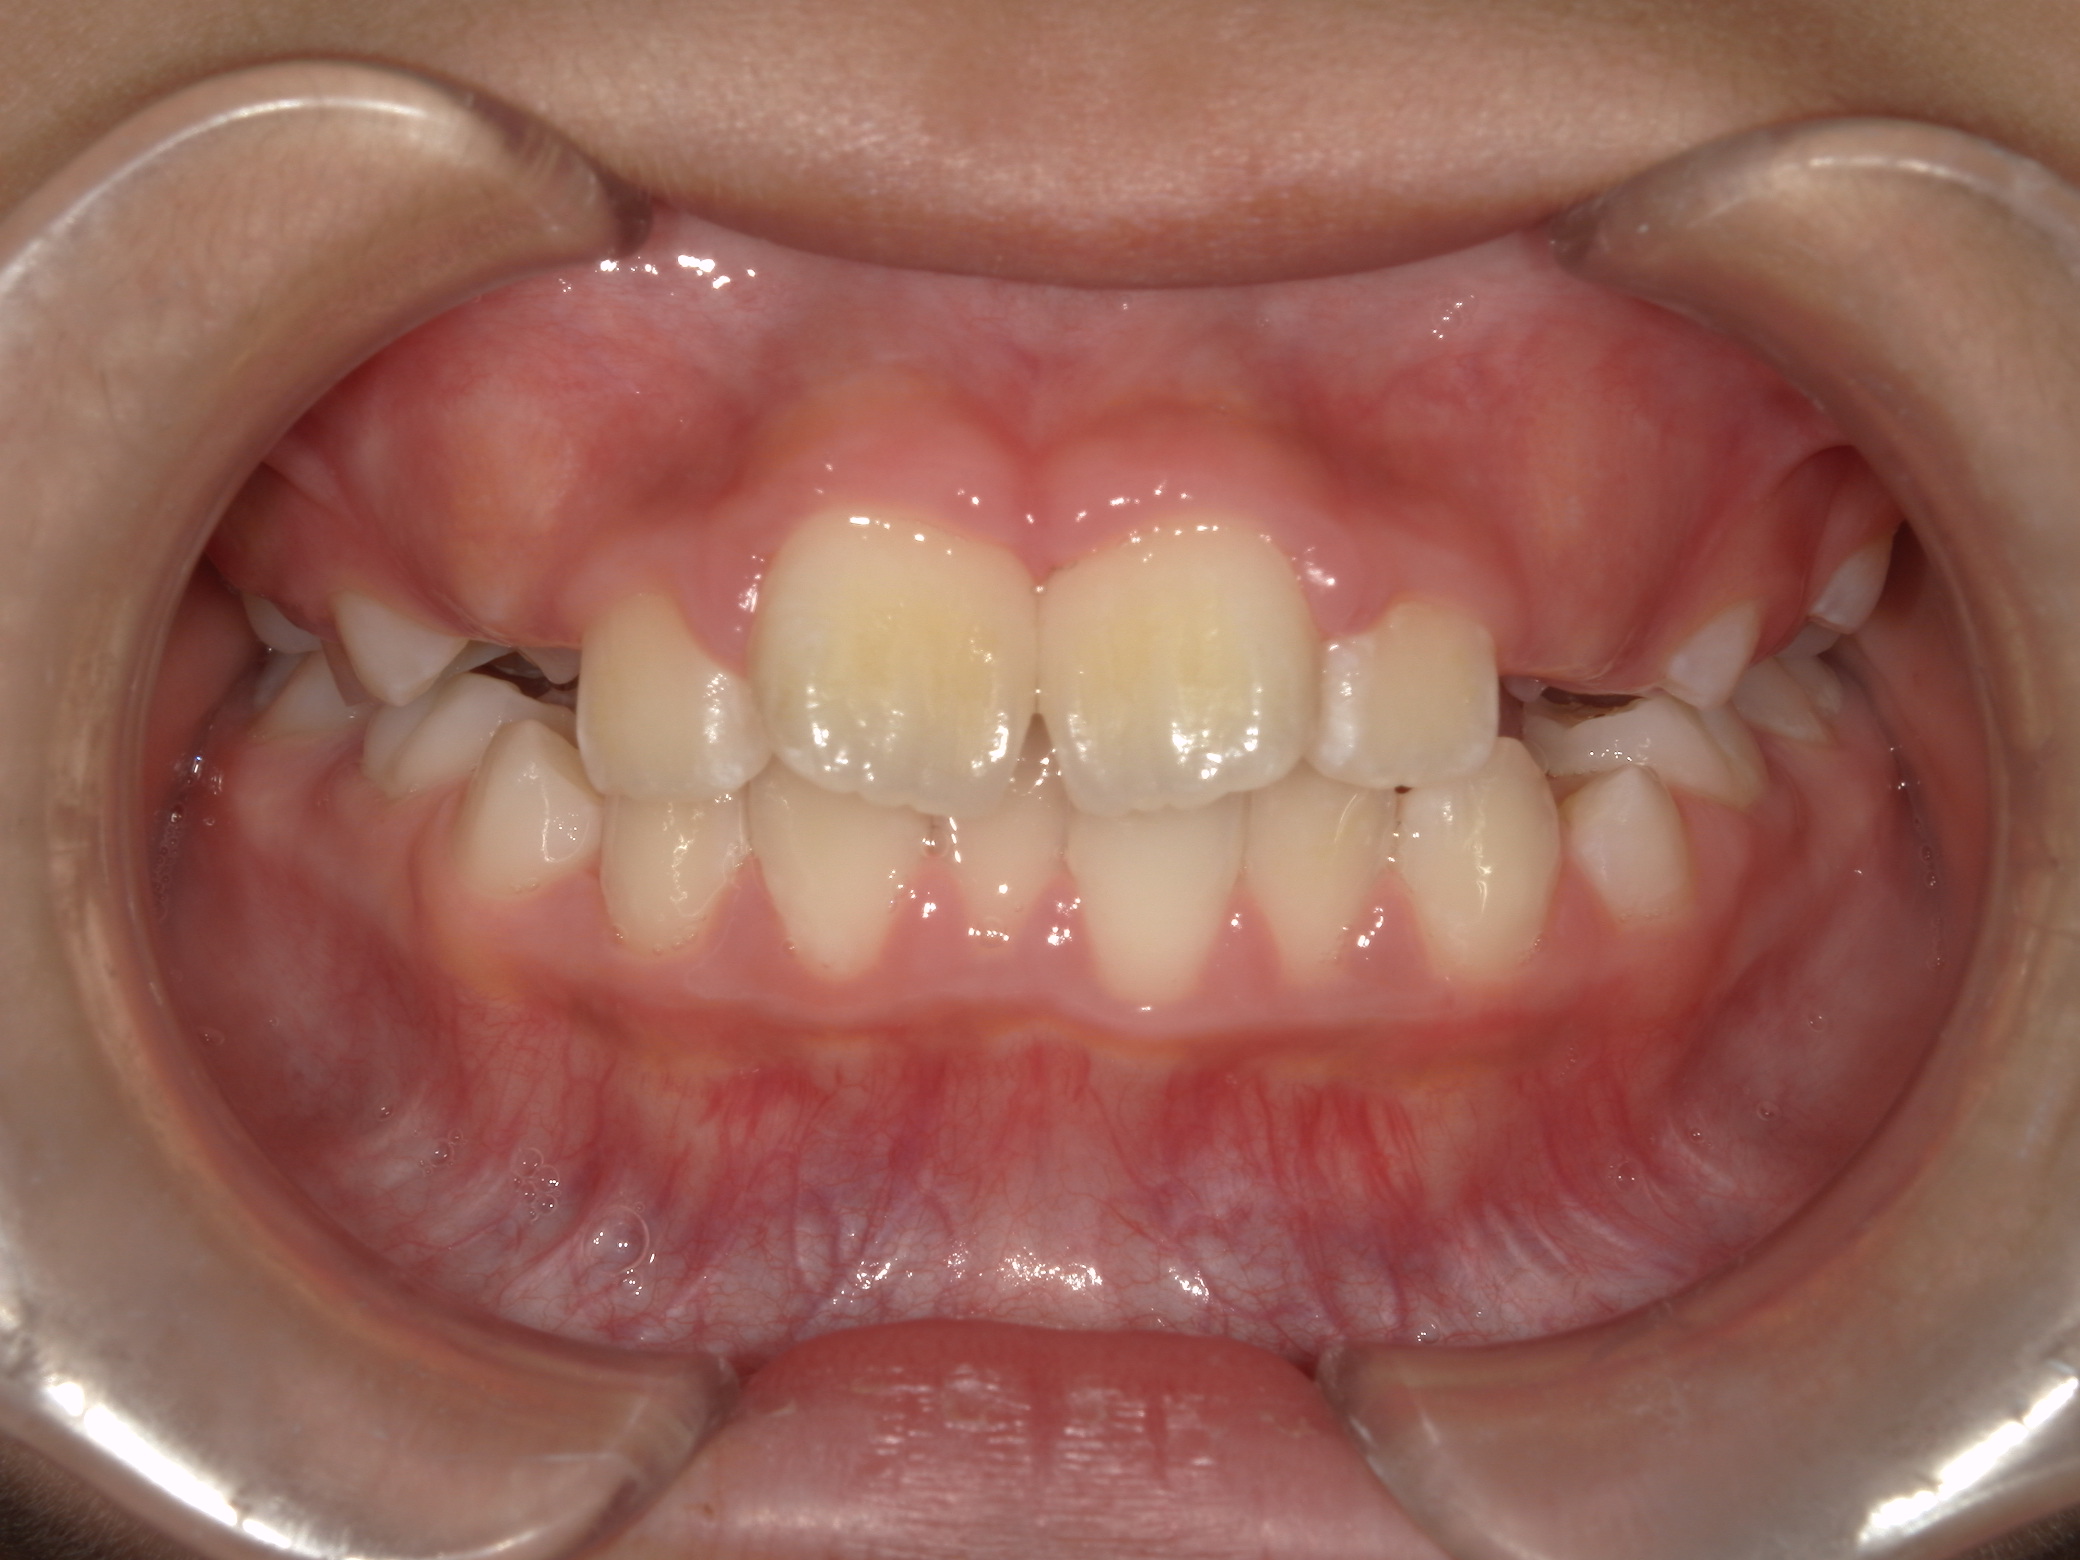

| 年齢・性別 | 8歳9ヶ月の男児 |

|---|---|

| 主訴 | 前歯の咬み合わせが逆になっており、歯根や歯肉への影響を懸念されて来院された患者様です。 |

| 治療期間・回数 | 3年7ヶ月・20回 |

| 費用 | 460,000円(税別) |